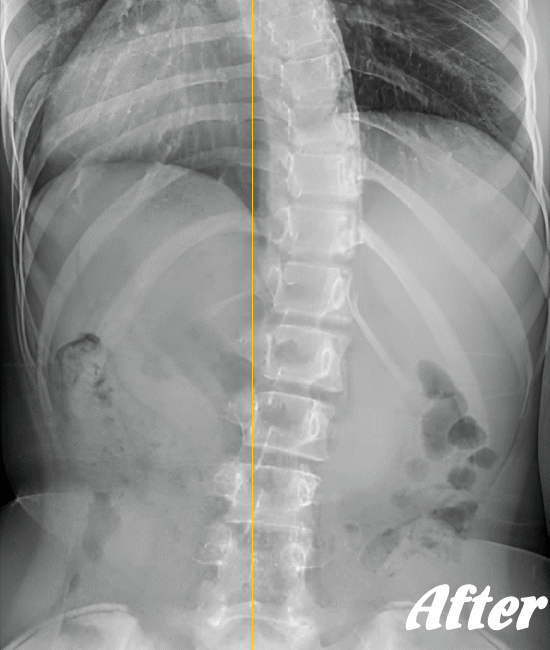

病院では、側弯の程度はレントゲンによる画像検査で弯曲の程度を調べます。

Cobb角(コブ角)とは、背骨の曲がり具合の角度を表す用語ですが、コブ角が10~25度程度なら経過観察。コブ角が25°~40°程度ならコルセットなどの装具を装着する療法、コブ角が40°~50°以上であれば手術…といった目安になります。

先天性や弯曲角度が大きい突発性側弯症は適応外になりますが、普段の姿勢の悪さに起因する機能性側弯症や初~中期の突発性側弯症であれば、施術対象になります。

ただし、弯曲が20°以上になると改善が難しくなってきます。また、脊柱(背骨)が側屈しているだけなら良いのですが、椎骨が回旋してしまっている場合の改善は、肋骨の変形もともなうため改善が難しくなります。